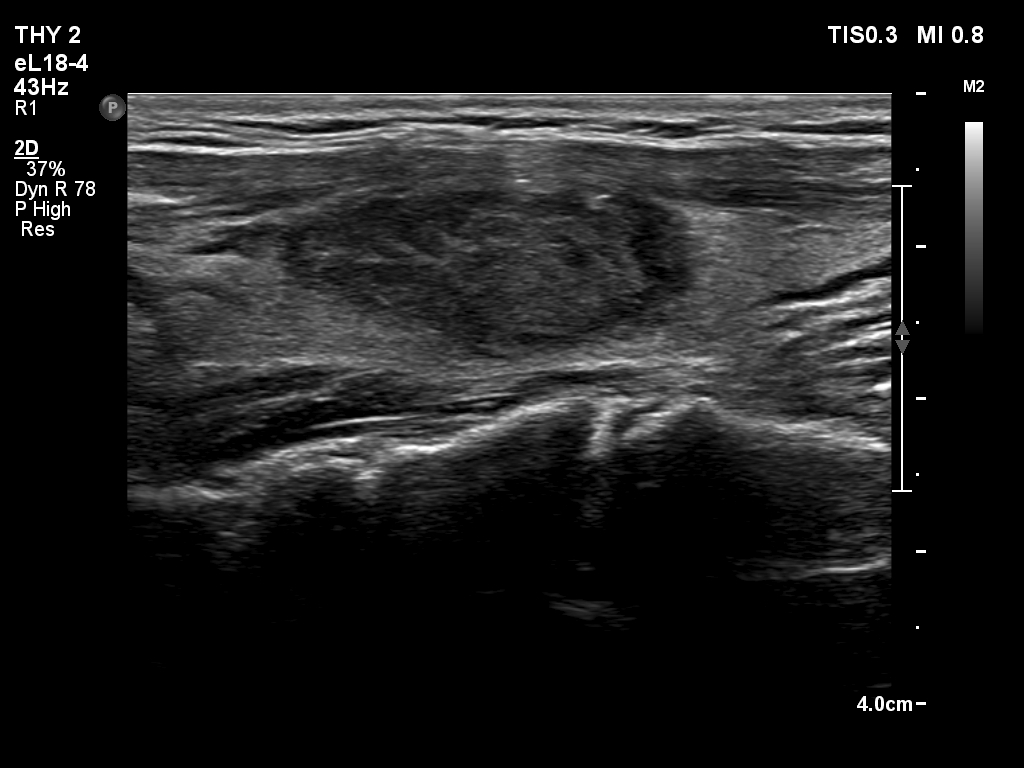

Two months after the sclerotherapy (sixth row of images):

Clinical presentation. The patient had no complaints.

Palpation: no abnormality.

Result of blood test: TSH 1.95 mIU/L.

Ultrasonography. The nodule has become much smaller. A heterogeneous mass has replaced the cystic content. The nodule presented taller-than-wide shape, the borders became irregular, lobulated. The nodule became avascular.Suggestion: ultrasound in 4 months.

After the shrinkage of the nodule, both the shape and margins have become irregular, taller-than-wide sign and lobulation have appeared.

The solid part of the nodule became avascular after the first session of sclerotherapy.